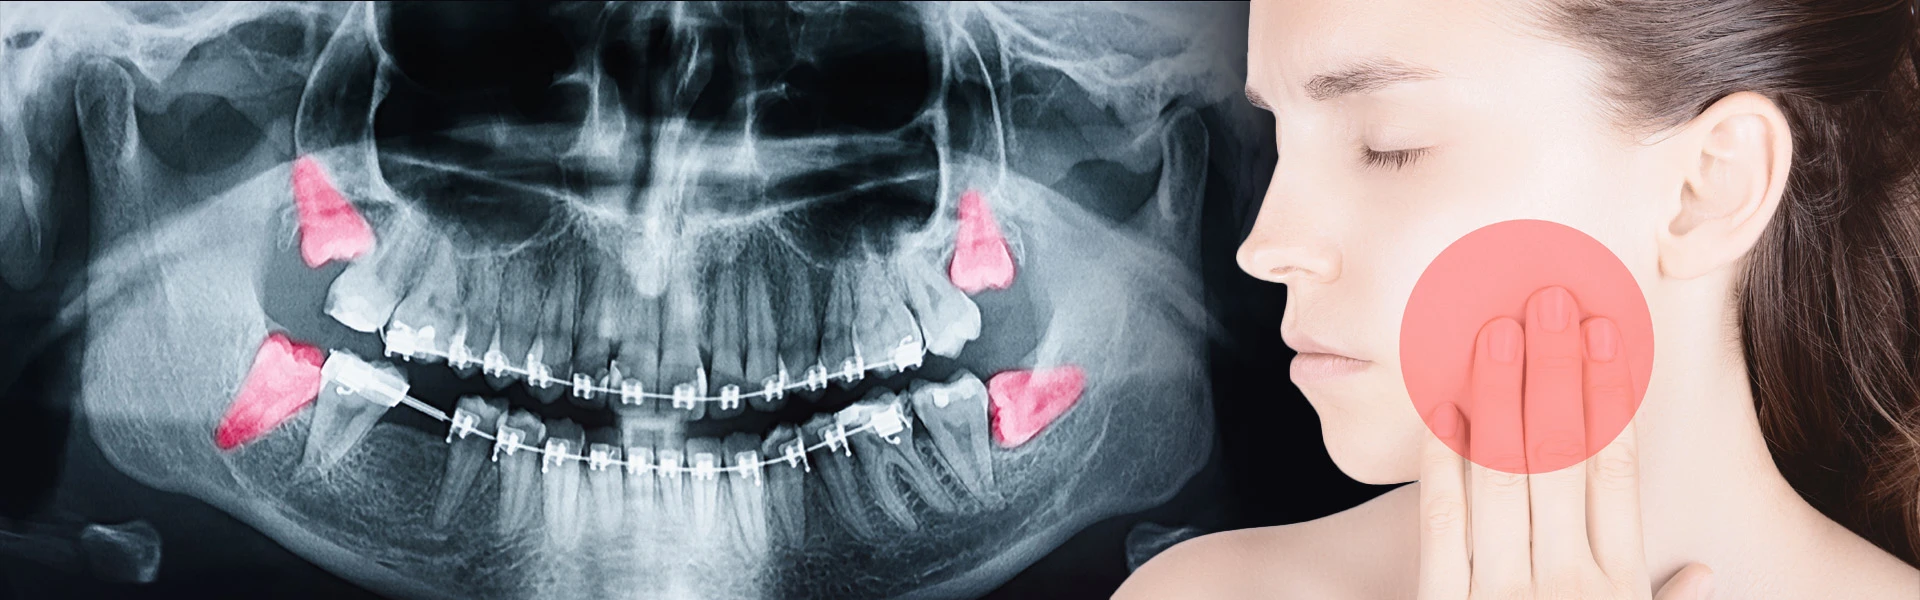

Umnjaci (osmice) su zubi koji najčešće “prave dramu”. Nekome nikad ne zasmetaju, a nekome izazivaju upalu, bol, otok, neugodan zadah, pa čak i pomjeranje zuba. Problem je što se umnjak često javlja “u talasima”: danas boli, sutra prestane, pa se čovjek ponada da je prošlo. A ispod površine, upala se može vraćati i postajati sve teža.

Šta je umnjak i zašto često pravi problem

Umnjak je treći kutnjak, posljednji zub u nizu. Najčešće niče kasnije (u kasnoj adolescenciji ili ranim dvadesetim), kada u vilici često nema dovoljno mjesta.

Zbog toga umnjak može:

- niknuti samo djelimično (dio ostane pod desni)

- niknuti pod uglom i “gurati” susjedni zub

- ostati potpuno u kosti (impaktiran)

- praviti džep ispod desni gdje se zadržavaju bakterije i hrana

Sve ovo povećava rizik upale i karijesa, i na umnjaku i na “sedmici” ispred njega.